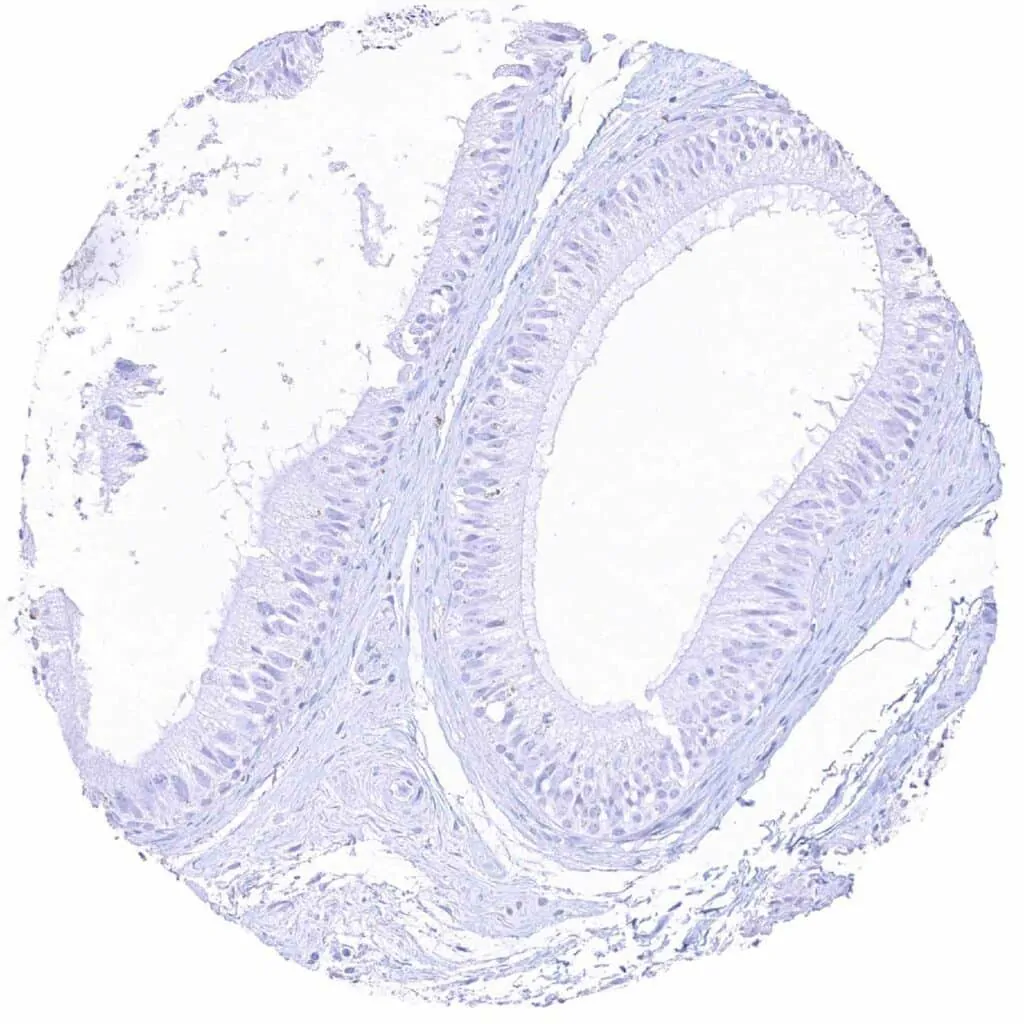

Uterus, endocervix